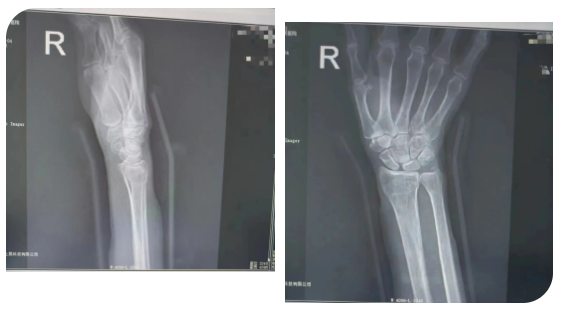

马女士(化名)于2年前因外伤导致“右侧桡骨远端骨折”,找当地赤脚医生行“包草药”治疗。后逐渐发现右侧腕部尺侧凸起畸形,腕关节尺偏活动受限,患者未予重视。

近3月来,患者抱孙子后出现右尺侧腕关节疼痛,前臂旋前时疼痛加重,握力减弱明显,感受到身体的异样后,便到医院创伤外科就诊。

患者于门诊善相关检查后诊断为:右侧尺骨撞击综合征。创伤外科主任医师王磊及其团队在仔细评估后,经过周密的术前准备,在臂丛麻醉下行“右侧尺骨短缩截骨”。该术式通过恢复中立或负向的尺骨变异来解压尺腕关节从而缓解尺骨撞击症状。